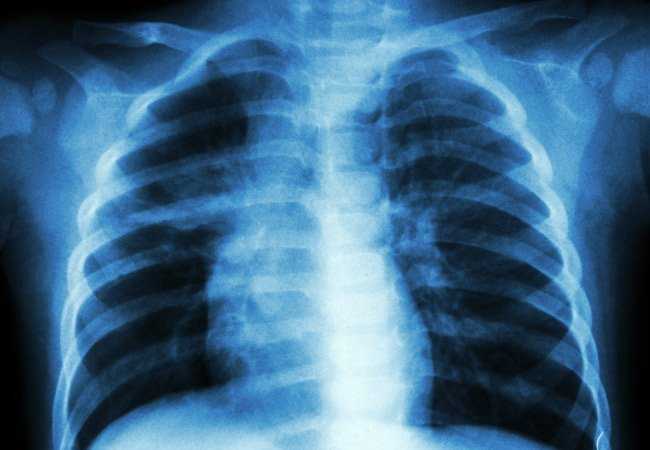

Η 19χρονη πάσχει από ιδιοπαθή υπέρταση πνευμονικής αρτηρίας.

Όπως αναφέρει δημοσίευμα της Βρετανικής Daily Mail, στην αρχή οι γιατροί σάστισαν όταν η πρώην τσιρλίντερ άρχισε να ανεβαίνει σκαλιά αναπνέοντας με δυσκολία και με πόνους στο στήθος.

Πριν από έναν χρόνο έγινε η διάγνωση και η η νεαρή κοπέλα άρχισε να ακολουθεί μια θεραπεία η οποία όμως δεν έχει μπορέσει να λύσει το πρόβλημα της.

«Πριν από έναν χρόνο άρχισα να αισθάνομαι άσχημα. Δεν μπορούσα να αναπνεύσω εύκολα. Κυριολεκτικά έμενα από ανάσα όταν ανέβαινα μια σκάλα. Έπρεπε να σταματάω καθώς ήμουν συνέχεια κουρασμένη. Με πονούσε το στήθος μου και τα πόδια μου πρήζονταν, οι γιατροί όμως μου έλεγαν ότι δεν έχω κάτι».

«Δεν έκανε πολλά. Το επόμενο στάδιο είναι η μεταμόσχευση πνευμόνων και ίσως καρδιάς. Αλλά κανείς δεν ξέρει πώς θα έρθουν τα πράγματα», όπως είπε η ίδια.